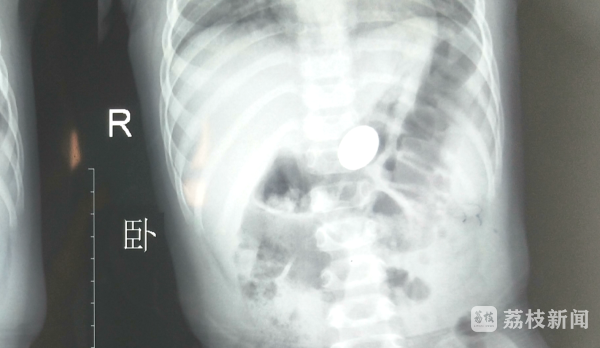

医生立刻为天天进行了相关检测,X光片显示,天天的食管里竟然有一个直径19mm的疑似金属物体。

此时,天天的父母才恍然大悟,天天在五天前曾玩过一个一角的硬币,可能那时候硬币被天天误吞了。硬币卡在宝宝体内五天了,食道壁已经出现变化,情况十分危急。